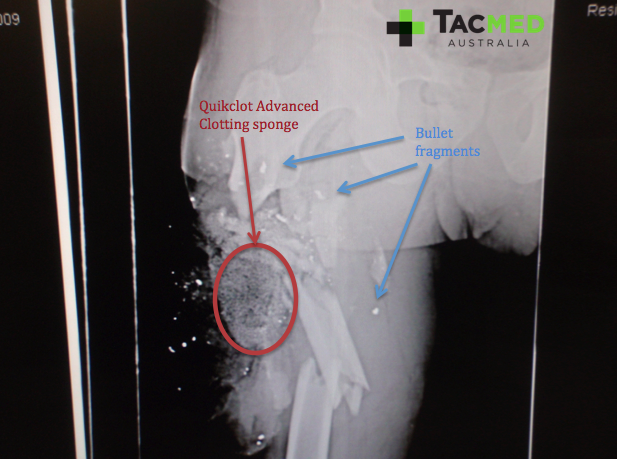

As the enemy combatant was incapacitated by the wound, he was no longer considered a threat and therefore, in accordance with the Geneva Convention, was to be afforded the same medical care as one of our own. On initial review, the treating medic noted the massive lateral thigh wound to be bleeding significantly, but assessed the wound as being too high for effective arterial tourniquet placement. He therefore opted for the use of a hemostatic dressing, which in those days came in the form of a QuikClot advanced clotting sponge (ACS). For those of you who weren’t around in the days prior to QuikClot combat gauze, the ACS was a precursor dressing to the combat gauze, and consisted of a teabag-like structure filled with small granules of hemostatic dressing.

The medic at point of injury packed an ACS into the wound and then applied a pressure dressing over the top, effectively stopping the bleeding. One downside to the ACS, which has been solved with the combat gauze, was that it was thermogenic when it contacted blood, and would often cause significant additional pain to the casualty as it burned, as well as damaging tissues in direct contact to it. The operation was nearing completion at the time the casualty was hit, so rather than call for a dust-off bird, the casualty was extracted back to the forward surgical team (FST) with the ground force.

As with any limb injury, a high priority was to assess for blood flow distal to the wound in order to ascertain if the major blood vessels had been damaged. Remarkably, the casualty had normal blood flow to his feet, implying that the femoral artery was intact. Next came an X-ray to have a look at the underlying bone structures. The casualty had minimal movement in the leg at time of review, and we expected him to have a fracture of his femur underlying the injury. The following images of the X-ray highlight the main features, including the shattered femur from where the bullet struck, the bullet fragments from where the projectile had disintegrated on impact, and the granular material of the ACS.